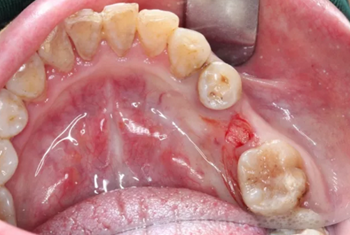

病例概述:48歲女性患者,口內(nèi)健康狀況良好,#35缺失多年,牙槽嵴頂骨寬度較窄。

#35缺失多年,導(dǎo)致#34向#35傾斜。

臨牙間距不足,因此,對種植體的位置要求極高。

1.碘伏浸泡消毒后的導(dǎo)板在患者口內(nèi)試戴,就位準確、十分穩(wěn)固。

2.使用牙齦環(huán)切刀施行不翻瓣手術(shù),創(chuàng)傷小,保護患者牙齦軟組織形態(tài)。